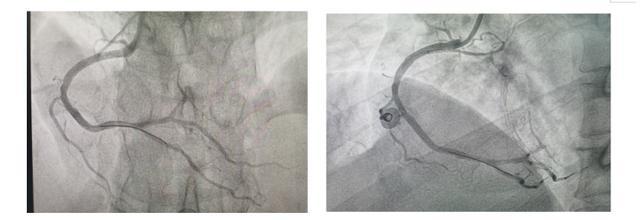

急诊冠脉造影提示前降支近段闭塞,远端见自身桥侧枝供血,回旋支中段闭塞,右冠近段闭塞伴血栓影。

在介入导管室的配合下,何文华主任医师带领介入团队成功植入IABP,之后针对粗大的右冠脉进行血栓抽吸、冠脉内溶栓、球囊扩张、硝普钠预防无复流、慢血流、植入支架等一系列操作,成功开通了右冠脉并恢复了三级血流。

(▲术前)

(▲术后)